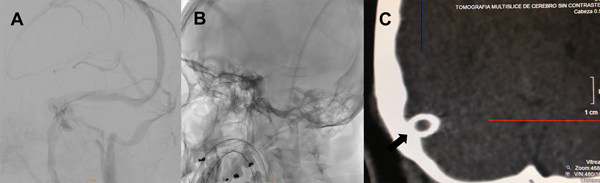

Le indicamos clopidogrel 75mg/día y AAS 100mg/día desde una semana antes del procedimiento. Bajo anestesia general le realizamos un abordaje arterial radial derecho y un abordaje venoso femoral derecho con introductor 5Fr. Se anticoaguló con 10.000 UI de heparina. Bajo guía 0.035 se realizó el recambio del introductor femoral por una vaina carotídea 6Fr progresando la misma hasta el golfo de la yugular derecha. Bajo una guía hidrofílica 0.035 ascendimos un catéter de acceso distal 6Fr hasta el seno sigmoideo derecho (figura 3A). Luego realizamos la angiografía cerebral para determinar el segmento venoso estenosado. Sobre una guía 0.014 localizada en el seno longitudinal superior, bajo roadmap navegamos con técnica rapid exchange un stent balón expandible de cromo-cobalto de 7 por 18mm (Herculink, Abbot) (figura 3B). Una vez localizado el stent a nivel de la estenosis insuflamos el balón con 11 atmósferas hasta llevar el segmento estenosado a diámetros similares a los adyacentes al mismo (figura 3C y 3D). Luego de implantado el stent, realizamos la presurometría del segmento angioplastiado evidenciando un gradiente de presión de 2mm de Hg. Se realizaron todos los controles angiográficos y se retiraron los catéteres arterial y venoso, también se realizó TC de cerebro sin evidencia de complicaciones (figura 4).

Figura 4: A) Angiografía cerebral digital con adquisición oblicua anterior izquierda en tiempo venoso luego de la impactación del stent en donde se observa el seno transverso derecho sin estenosis residual. B) Radiografía de cráneo en incidencia oblicua anterior izquierda donde se observa el stent abierto implantado en el seno transverso derecho. C) TC de cerebro. Reconstrucción coronal del detalle témporo-occipital derecho. La flecha negra muestra el stent abierto implantado en el seno transverso derecho.